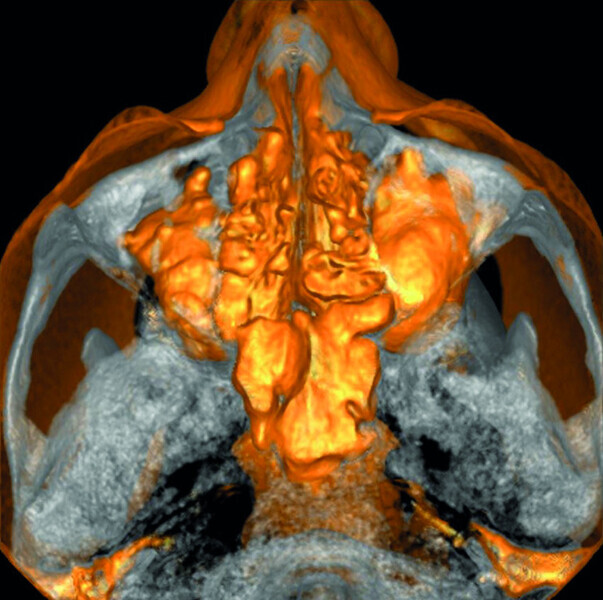

Maxillary sinus and root canal therapy complications